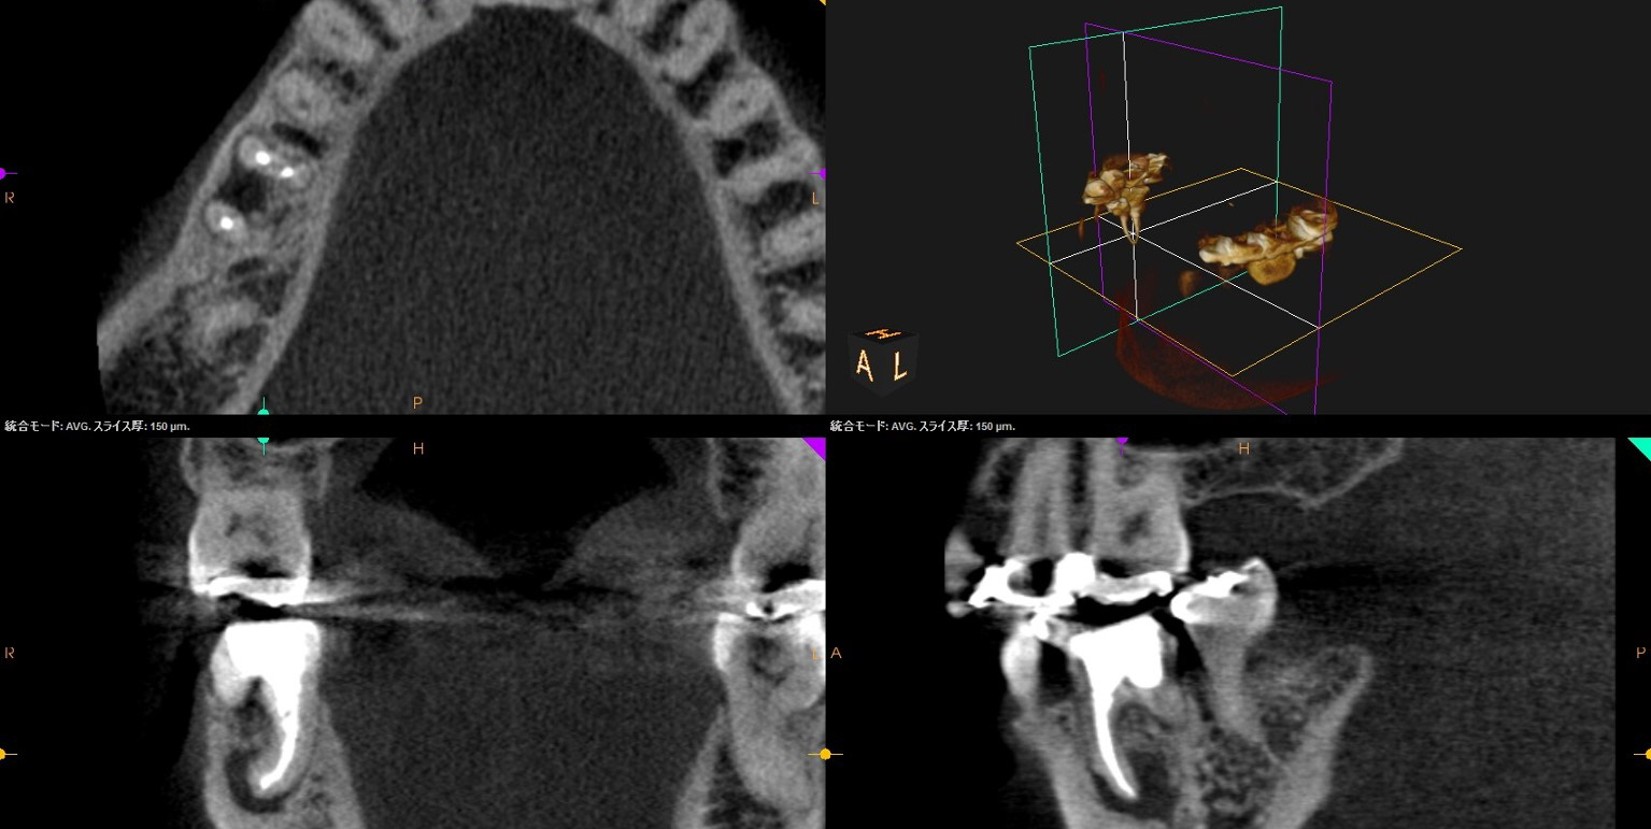

• 初診来院時 根尖性歯周炎により骨吸収あり

• 自費の感染根幹治療終了直後

• 自費感染根幹治療6か月後、骨の回復がみられた

• CT撮影による三次元診断で、見落としのない精密治療